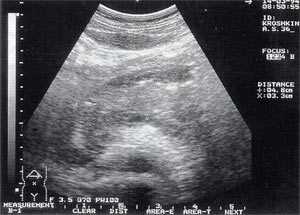

- увеличение размеров поджелудочной железы (рис. 1) - отмечено в 88% случаев. Нормальные размеры поджелудочной железы: головка 3-4,5 см; тело 2,5 - 3 см; хвост 3-4 см;

- увеличение расстояния между задней стенкой желудка и передней поверхностью поджелудочной железы свыше 3 мм и достигающее 10 - 20 мм, что характеризует отек парапанкреатических тканей, отмечено в 53% наблюдений (рис. 1);

Рис. 1. Острый панкреатит, деструктивная форма. Увеличение размеров поджелудочной железы, нечеткость контуров, увеличение расстояния между задней стенкой желудка и поджелудочной железы.